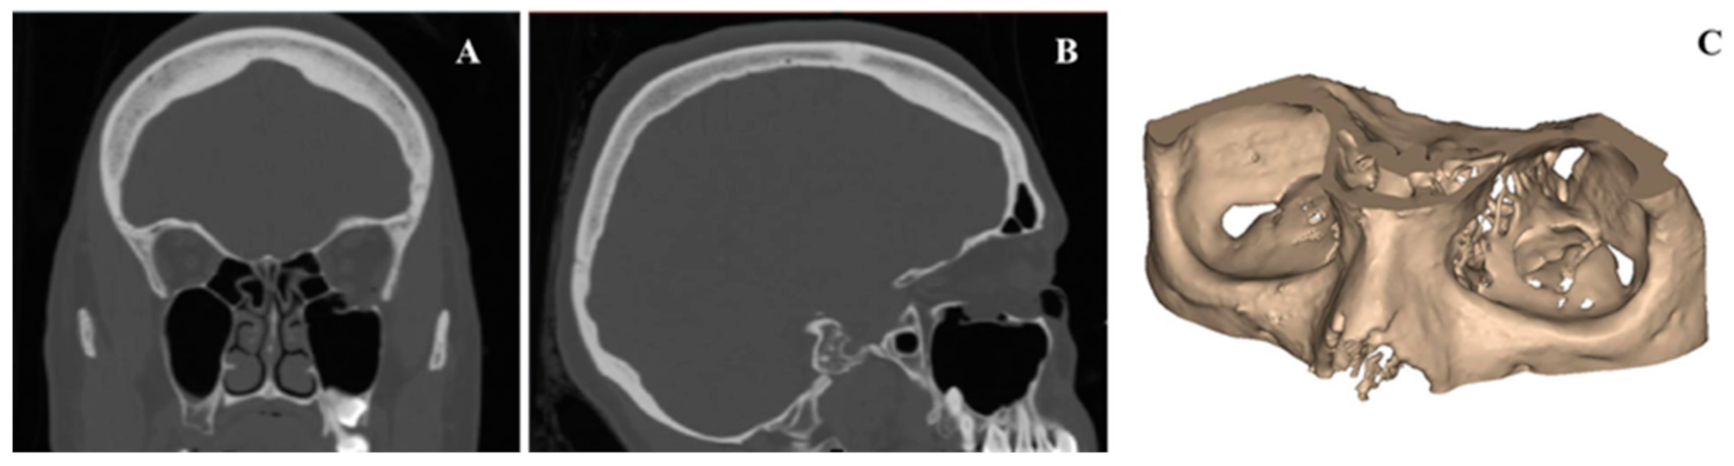

2.1. Medical Image Processing and Modeling of Patient-Specific Orbital Implants